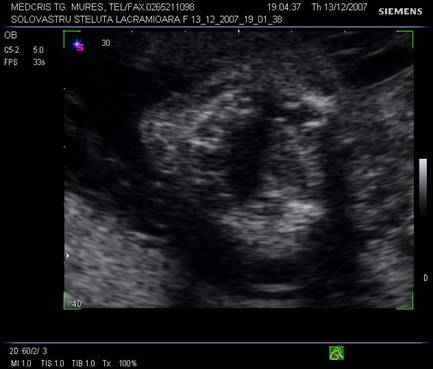

Linia de mijloc hiperecogena frontoocipitala este formata anterior si posterior de falx cerebri si fisura interemisferica, central de septum pellucidum. La sfarsitul primului trimestru de sarcina, linia de mijloc hiperecogena este flancata la distanta de o pereche de ventriculi laterali, ce inconjoara plexurile choroide ecogene. Din saptamana a 15-a cresterea cortexului devine vizibila, la marginea ventriculilor laterali, ca o margine hipoecogena. Partea posterioara a ventriculilor laterali ramane ocupata de plexurile choroide, in timp ce coarnele anterioare contin doar fluid. Dupa saptamana 19-a ventriculii laterali au caractere constante pe tot parcursul sarcinii.[1,3,8,13,14]

Planul I - cel mai inalt plan axial. Cortexul cerebral hipoecogen localizat intre linia de mijloc si craniu.

Planul

II demonstreaza ventriculii laterali hipoecogeni si parte din plexurile

choroide ecogene.

Planul III sau planul frontooccipital, pentru masurarea diametrelor biparietal si frontoocipital. Ecoul de mijloc frontoocipital este intrerupt in zona cavum septum pellucidi, anecogena, situata anterior de ventriculul III. Acesta este situat intre doi nuclei talamici hipoecogeni si apare ca o despicatura mica sau o linie.